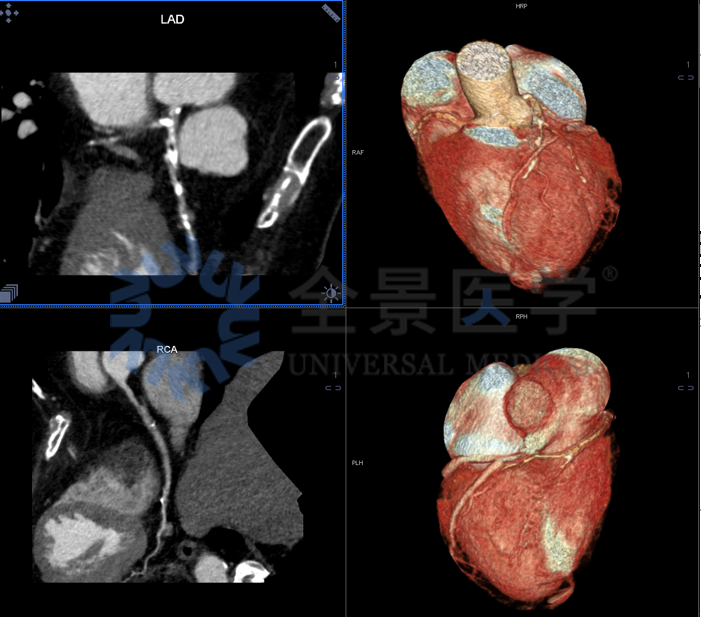

67 岁,女性,糖尿病十余年病史

冠状动脉 CTA 显示:冠状动脉钙化积分 525.1 分;

冠心病:①左前降支多发斑块形成,管腔重度狭窄;②右冠状动脉多发斑块形成,管腔轻‐中度狭窄;③左主干、左旋支偏心钙化斑块形成,管腔未见狭窄。